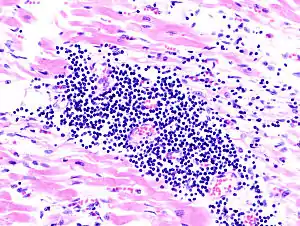

![]() Гістопатологічне зображення міокардиту при аутопсії (розтині) пацієнта з гострою серцевою недостатністю Гістопатологічне зображення міокардиту при аутопсії (розтині) пацієнта з гострою серцевою недостатністю | |